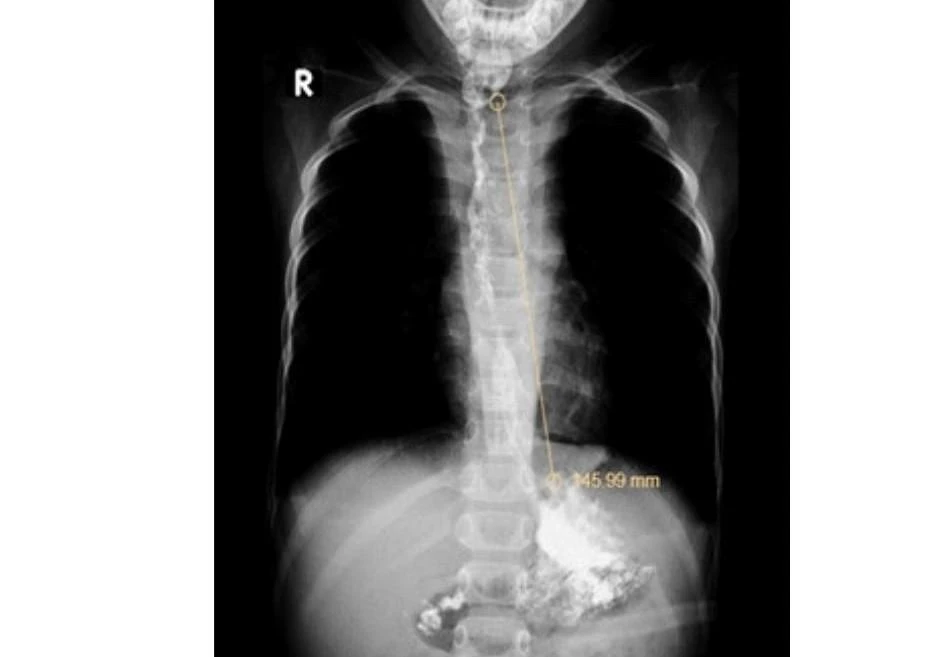

| Hình ảnh lòng thực quản hẹp, thành nham nhở toàn bộ đoạn thực quản ngực và đoạn bụng của bé. Ảnh: BVCC |

Tai nạn đã khiến bé trai bị hẹp toàn bộ thực quản ngực, không thể ăn bằng đường miệng, phải mở dạ dày và đặt ống nuôi ăn.

Trải qua nhiều lần nong thực quản, mổ cắt nối thực quản nhưng vẫn tái hẹp, bé phải phẫu thuật thay thế thực quản bằng dạ dày. Hiện bé trai đã ăn uống lại được nhưng vẫn tiếp tục tái khám, theo dõi.